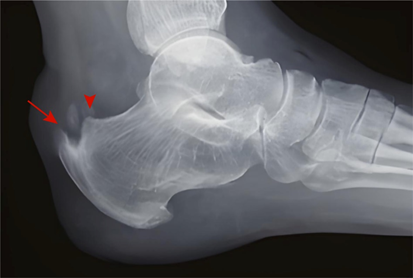

▶X线检査:可见跟腱止点处钙化、骨化等病变,严重者可见跟骨后上突增生(Haglund畸形)。

图4:X线检査可见跟腱止点处钙化增生(长箭头), 跟骨后上突增生(箭头)